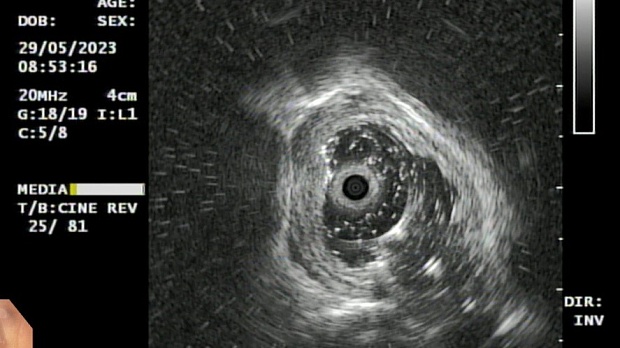

Иллюстрация №3: Эндофото. Сидероз нижней трети пищевода, эндоскопическая ультрасонография

Согласно полученным данным - в среднегрудном и нижнегрудном отделах пищевода определялась проксимальная граница плоских неправильной формы поверхностных рубцов суммарной протяженностью до 8,0 см. На этом фоне в зонах поверхностных рубцов по задней полуокружности визуализировались участки гиперпигментации в темный цвет (Рис. 1). При исследовании в режиме Dual Focus было отмечено наличие мелких (до 0,001 см) черно-коричневых включений, расположенных субэпителиально - в строме слизистой оболочки, сливания их в единый конгломерат не определялось (Рис. 2). При эндосонографии с применением минидатчика с частотой сканирования 20МГц выявлено, что все слои стенки четко дифференцируются, не утолщены, в слизистой оболочки визуализированы мелких гиперэхогенные включения с эхотенями (Рис. 3).

В пищеводе в шейном его отделе на уровне 16 см от резцов циркулярно визуализированы единичные синюшные флебоэктазии размерами до 0.5 см. Дистальнее пищевод визуально не изменен до уровня 28 см от резцов, где определяется проксимальная граница плоских неправильной формы поверхностных рубцов, распространяющихся до уровня 36 см от резцов. На этом фоне в зонах поверхностных рубцов по задней полуокружности визуализированы участки гиперпигментации в черно-коричнеый цвет. При осмотре в режиме Near Focus с увеличением - между зон пигментации определяются расширенные капилляры типа II по Inoue-классификации. При биопсии отмечена десквамация плоского эпителия, визуализированы мелкие черно-коричневые включения в строме слизистой оболочки, размеры их до 0,001 см, сливания их в единый конгломерат не отмечается. При эндосонографии с датчиком 20Мгц в исследуемой зоне в слизистой оболочке определяются гиперэхогенные включения, в то время как в подслизистом слое - зоны со сниженной эхогенностью. При биопсии отмечается уплотнение ткани, однако истинной фрагментации не определяется. Уровень Z-линии совпадает с уровнем анатомического кардиоэзофагеального перехода. Розетка кардии эластичная, смыкается не полностью, расположена на уровне пищеводного отверстия диафрагмы.

Заключение: Эндоскопическая и эндосонографическая картина трудна для трактовки: следует дифференцировать сидероз слизистой оболочки пищевода на фоне постэрозивных рубцов и меланоз пищевода